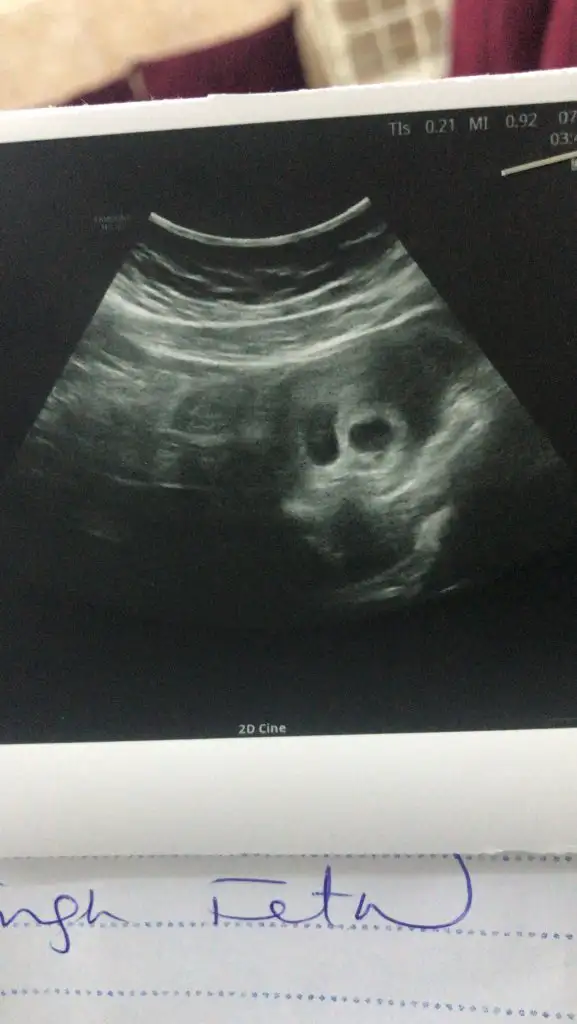

iki kesemii var cnmmm ben mi yanlis goruyomDayanamadim özele gittimbak foto ekledim

Evet canim iki keseiki kesemii var cnmmm ben mi yanlis goruyomyaaa iyi yapmissiin annesiii allahim devaminida saglikla sihhatle nasip etsin hepimize bnde heycandan uyuyamiyrm sabh gdcn bnde